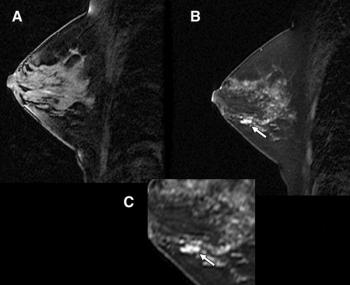

Breast cancer detection rates increase substantially when women at high risk and those with dense breasts undergo mammography and ultrasound annually, according to a study presented Wednesday at the 2009 RSNA meeting. MRI is an even more effective technique when used with mammography, but only for women who are at high risk for the condition.

Targeted breast ultrasound is less invasive and expensive than biopsy, as well as reduces anxiety over breast cancer screening.